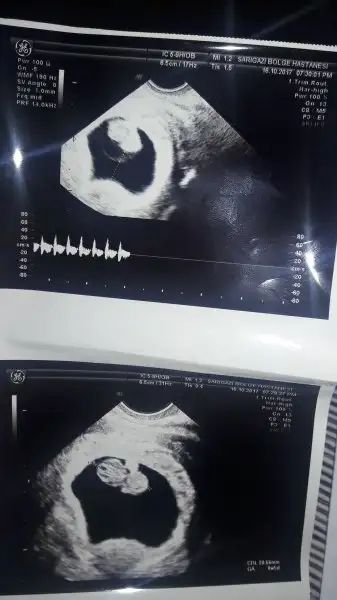

hatta benim maymun 1 hafta önden gidiyor 10+2 olmamız gerekirken 11+1 çıktı doktor hemen ikili testi yaptı cinsiyet tahmininde de bulundu erkek gibi dedi 4kasım da cinsiyet randevumuz var